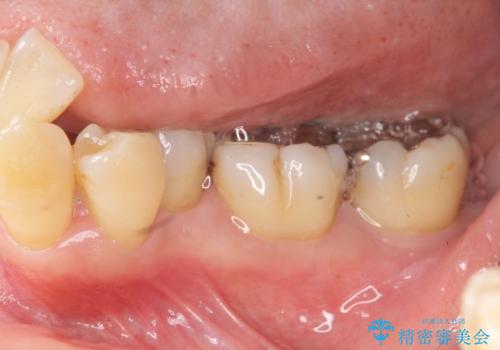

歯周ポケットの除去を併用したセラミック治療